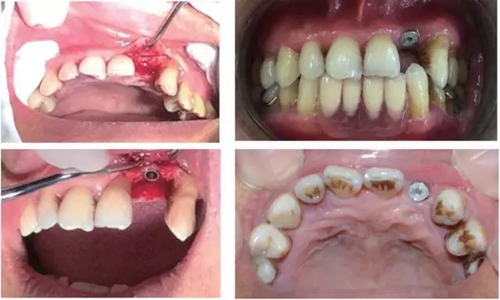

行影像學檢查(圖2);種植一枚Zuga 3.5*10 mm種植體,扭力≥35 N•cm,旋入愈合基臺(healing abutment)(圖3、4)。

圖3 22種植術(shù)前后照片

圖4 種植術(shù)后影像學檢查

3個月后,分別使用傳統(tǒng)的轉(zhuǎn)移桿硅橡膠取模以及口內(nèi)掃描取模進行修復(圖5~8)。